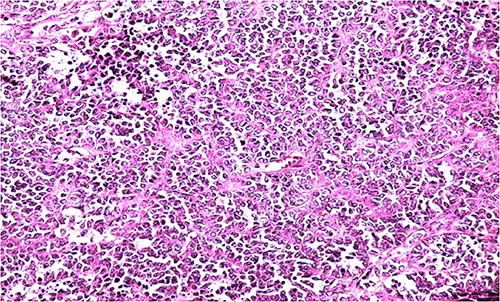

Biologically, the CA 125 tumor marker was at 126.2 IU/ml. The patient underwent a left adnexectomy and an omentectomy (small omentum). Macroscopically, the ovarian mass was smooth on the surface and fleshy on section with the presence of necrotic and hemorrhagic changes. On the histological level, the tumoral proliferation presents a diffuse architecture formed by sheets and clusters separated by fine fibrous septa. Tumor cells are rounded, small, and monomorphic with hyperchromatic, finely nucleolated nuclei and reduced cytoplasm. Mitotic activity is high (36 mitoses/10 HPF) (Figs 3 and 4). The samples taken from the small omentum were tumorous. An immunohistochemical study was carried out and showed diffuse positive expression by tumor cells of Vimentin, and focal by antibodies (Cytokeratin AE1/AE3, EMA, CD99, WT1, Inhibin, and SALL4) and an absence of expression by antibodies (CD45, Chromogranin, PAX8, and AFP) (Figs 5–7).

HE section showing diffuse sheets of small, closely packed round cells with scant cytoplasm separated by fibrous septa (x200).

HE section of small monomorphic tumor cells showing hyperchromasia and mitotic figures (x400).

The microscopic features consist of diffuse growth pattern made up of densely packed small cells and focal figures of follicle-like gaps with eosinophilic and, rarely, basophilic fluids. The majority of the cancerous cells are small and hyperchromatic. The nuclei have a single tiny nucleoli and chromatin that is loosely clumped. The mitotic activity is high. If the tumors are widely sampled, larger cells might be seen in at least half of all SCCOHTs. We name it “large cell variant of SCCOHT” when it is exclusively formed by large neoplastic cells. These cells have “rhabdoid” characteristics like eccentric nuclei with conspicuous nucleoli, and glassy eosinophilic cytoplasm. Small foci of mucinous glands or cysts walled by mature epithelium, signet-ring cells, or atypical mucinous cells are present in about 12% of cases [2].